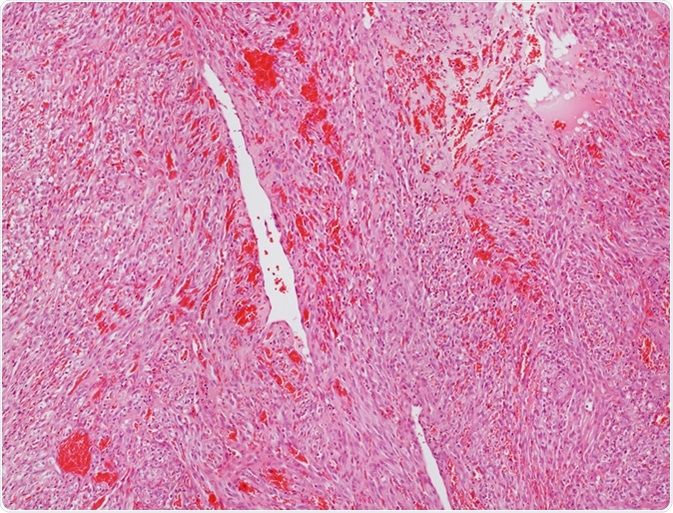

Microscope picture of an angiosarcoma. Image Credit: Convit / Shutterstock